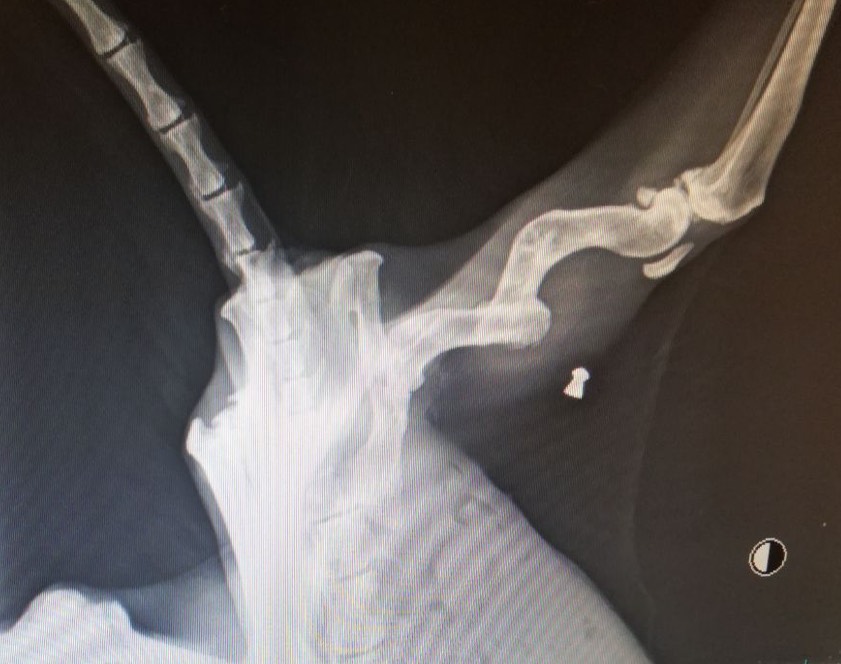

Bei den anschließenden Röntgen-Untersuchungen zeigten sich laut einer aktuellen Mitteilung des Tierschutzvereins bei der Katze „nicht nur ein alter Oberschenkelbruch sowie ein Oberschenkelhalsbruch am anderen Bein, sondern auch ein noch in ihr steckendes Luftgewehr-Projektil“. Schübel: „Offensichtlich wurde auf die Katze geschossen. Zusätzlich liegt die Vermutung nahe, dass ihr auch die Brüche absichtlich zugefügt wurden.“ Die Tierschützer veröffentlichten dazu auch ein Röntgenbild.

"Offensichtlich wurde auf die Katze geschossen. Zusätzlich liegt die Vermutung nahe, dass ihr auch die Brüche absichtlich zugefügt wurden."